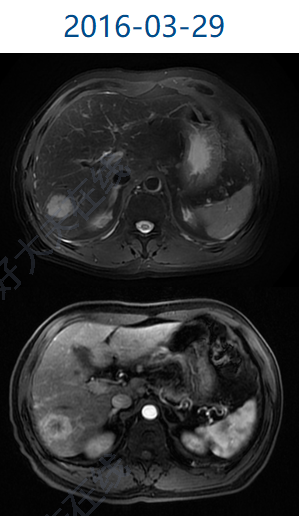

治療前 肝臟多發(fā)占位,考慮肝細(xì)胞癌伴肝內(nèi)多發(fā)子灶,肝中靜脈受累,門脈右支癌栓形成 治療后 治療后270天 TACE聯(lián)合索拉非尼治療后進(jìn)展,換用PD1(信迪利單抗)聯(lián)合瑞戈非尼治療,9療程后達(dá)到完全緩解,腫瘤治愈